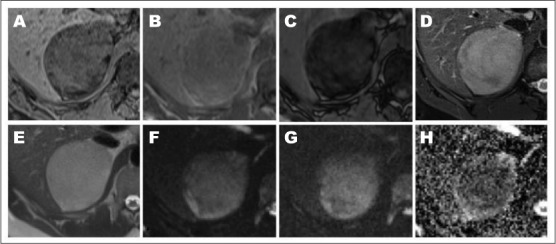

回顾以往针对不同临床指征进行的影像学研究,发现2001年和2011年右侧肾上腺肿物仅为1cm和4.4cm,在后续影像学研究中快速增长(图2)。2014年,无对比剂的腹部磁共振图像(评估肾功能不全)显示8.4 cm的右侧肾上腺肿物,呈T2信号,提示软组织信号强度。同相和反相T1图像和脂肪抑制序列分别证实了微观和宏观脂肪(图3)。2015年,无对比剂的计算机断层扫描(CT)显示进行性增大至9.6 cm和10.1 cm,可见大体脂肪。脾脏和骨性改变与已知的SCD一致。

图2

图3